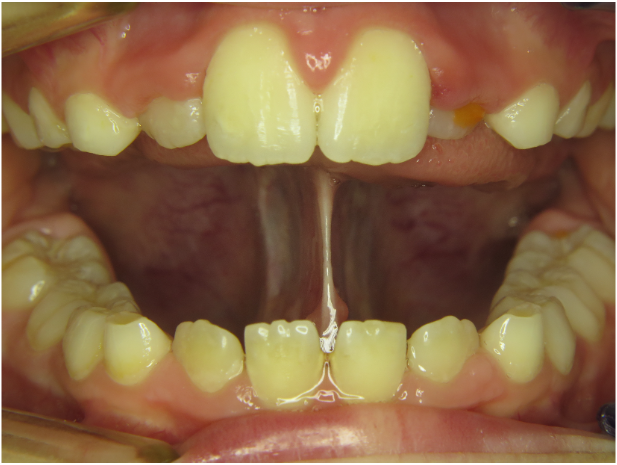

Wir sagten es bereits an anderer Stelle – Bilder sagen mehr als 1000 Worte…

Die Galerie zeigt verschiedene Problemstellungen unserer Patienten von Anfang bis Ende:

mykie® macht’s möglich – sehen Sie selbst: